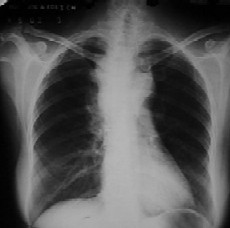

Fig.  36 años. APP: asmático,

alcohólico; tratamiento con Disulfiram. Ingirió bebidas alohólicas en

la mañana y refiere dolor retroesternal de instalación súbita que se exacerba

con el decúbito, disfonía y sensación de inflamación en el cuello. Afebril.

No disnea. EF: MV conservado, no estertores. ID: mediastinitis. Banda transparente paralela a la

SCV, con

otra banda, densa y fina (el pericardio) por fuera, por  neumomediastino. |